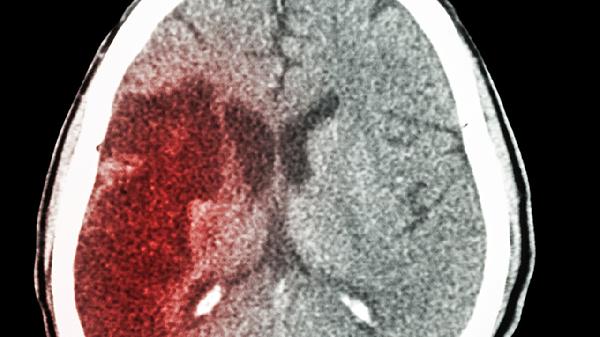

64岁的张阿姨最近总抱怨耳朵里有蝉鸣声,转头时偶尔天旋地转。女儿劝她去医院检查,她却摆摆手说:"人老了都这样,歇会儿就好。"直到那个清晨,她突然半边身子不能动,送到医院确诊为脑梗。主治医师看着CT片直摇头:"这些预警信号出现时就来,结果会完全不同..."

一、耳鸣头晕背后的危险信号

1、内耳供血不足的警.示

持续耳鸣可能是椎基底动脉供血不足的表现,这条血管负责小脑和听觉中枢供血。当血流减少30%时,就会出现蝉鸣样耳鸣。